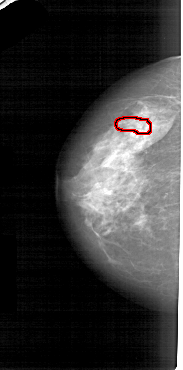

A_1553_1.RIGHT_CC

RIGHT_CC LINES 4936 PIXELS_PER_LINE 2476 BITS_PER_PIXEL 12 RESOLUTION 43.5 NON_OVERLAY

FILE: A_1553_1.LEFT_MLO.OVERLAY

TOTAL_ABNORMALITIES 1

ABNORMALITY 1

LESION_TYPE CALCIFICATION TYPE PUNCTATE DISTRIBUTION LINEAR

ASSESSMENT 4

SUBTLETY 1

PATHOLOGY BENIGN

TOTAL_OUTLINES 1

BOUNDARY